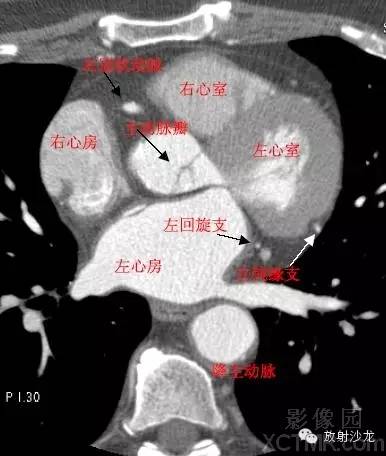

A.Aorta-Ascending Aorta升主动脉

LMA -Left Main Artery冠状动脉左主干

LCX -Left Circumflex Artery左回旋支

LMB -Left Obtuse Marginal Branch 左边缘支(钝缘支)

RCA -Right Coronary Artery 右冠状动脉

ConusBranch右动脉圆锥支

LAA –Left AtrialAppendage左心耳

CS -Coronary Sinus冠状窦

D. Aorta-Descending Aorta降主动脉